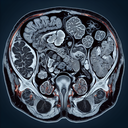

МРТ органів черевної порожнини

Магнітно-резонансна томографія (МРТ) органів черевної порожнини – це безпечний і неінвазивний метод діагностики, який використовує магнітні поля і радіохвилі для отримання детальних зображень внутрішніх структур тіла. ### Переваги МРТ: - **Висока якість зображень**: Забезпечує чіткі деталі м’яких тканин, що допомагає виявити патології, пухлини, запалення чи травми. - **Безпека**: Не використовує рентгенівське випромінювання...